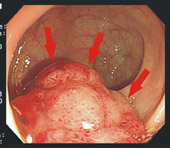

常見便秘的症狀及徵候如下:腹部的膨脹感、腹痛、腸脹氣,而且在排便之後才能得到緩解。便秘一旦慢性化,大腸內堆積的代謝廢物會導致沒有精神、噁心、嘔吐、口臭、食欲不振。當患者抱怨有便秘的情形,必須包括排便次數、糞便的型態、是否合併其他症狀或徵候等有意義的內容。診斷所需要的資訊如下:過去的臨床病史、藥物史、排便日記、評估便秘的等級、評估便秘、腹瀉的等級、記載糞便型態的等級、症狀與徵候的等級。大部分的便秘情形,只要評估病史加上簡單的身體檢查就可以正確的掌握病因及嚴重度,並確立治療方式。有時狀況不確定或症狀有變化時,會視情況安排進一步檢查,通常最簡便的是腹部X光檢查(圖一),可直接發現腸氣分佈與糞便堆積情形。此外,腸道構造上是否異常,也常常是老人便秘需考慮的重要原因,例如大腸是否長腫瘤或狹窄,然後再安排內視鏡(圖二)或者大腸鋇劑攝影,以尋找大腸內是否有憩室、息肉、或腫瘤等構造上的問題。此外,甲狀腺功能、血中電解質濃度、牙科檢查、神經學檢查等等也都能幫助診斷。

便秘的治療首重非藥物療法,也就是養成生活上一旦有便意就去上廁所的習慣,加上規律的生活與習慣性的適度運動,有時可以發揮功效。飲食習慣上,多攝取富含纖維的綠色蔬菜與國內盛產的香蕉和木瓜也是幫助排便的良方。排便日記是很有用的,不但可以了解各種活動與排便狀況、糞便型態變化的關係,透過關聯症狀及徵候的記載掌握排便的習慣,更可以根據排便日記評估治療的效果。至於便秘的藥物療法則為醫師裁量的範圍,一般的用藥分類如下:糞便成形促便劑、潤滑劑、刺激性緩瀉劑、滲透性壓瀉劑、神經肌肉藥物。絕大多數非特異性便秘的病人,在增加纖維質的攝取和水份的補充或藥物治療,都會逐漸獲得改善,若症狀依然存在甚至於加重則要注意是否腸道構造上有異常或腫瘤情形(圖二),進一步的檢查是不可輕忽的。

圖二.大腸腫瘤